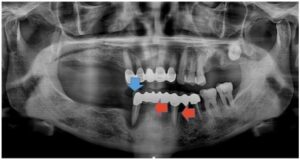

정밀한 검사를 위해

파노라마 사진을 촬영해 보았더니

아래턱 치아들이

심각한 골흡수를 보이고 있는

만성 치주염 상태로

전체 발치가 불가피한 상황이었습니다.

파노라마 촬영을 통해

임플란트가 정확한 위치와 방향으로

식립 된 것을 확인하였습니다.

모든 치료가 마무리된

파노라마 사진과

구강 내 사진인데요.